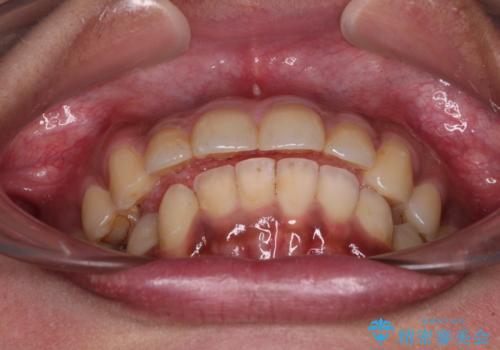

深い咬み合わせと前歯のデコボコ インビザラインによる矯正治療

治療途中では、左右ともに奥歯が咬みにくい状態が続き、問題なく噛めるようになるまでに長期間を要しました。

一方で、デコボコや下顎の前歯が隠れてしまうほどの深い咬み合わせはしっかりと改善されました。